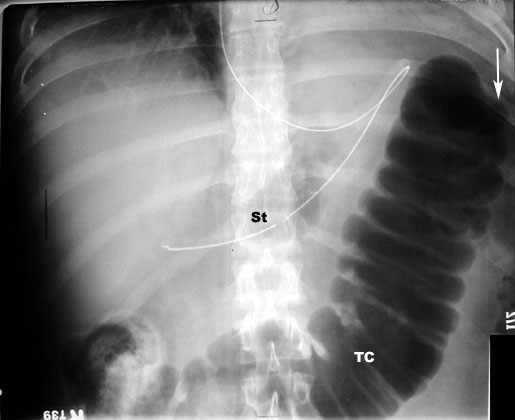

Acute Pancreatitis

Cut off sign and Ileus

• White arrowpoints to Transeverse colon cut off at Splenic flexure. No air in descending colon.

• TC: Transverse colon

• I: Represents small bowel loops with air suggestive of Ileus